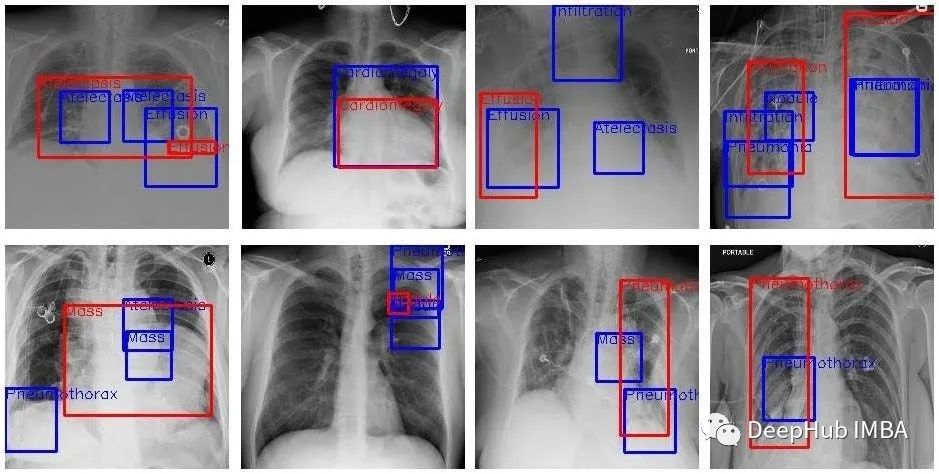

医疗保健:医院可能会使用 ML 系统来分析患者数据,并根据某些 X 射线预测患者患某种疾病的可能性。